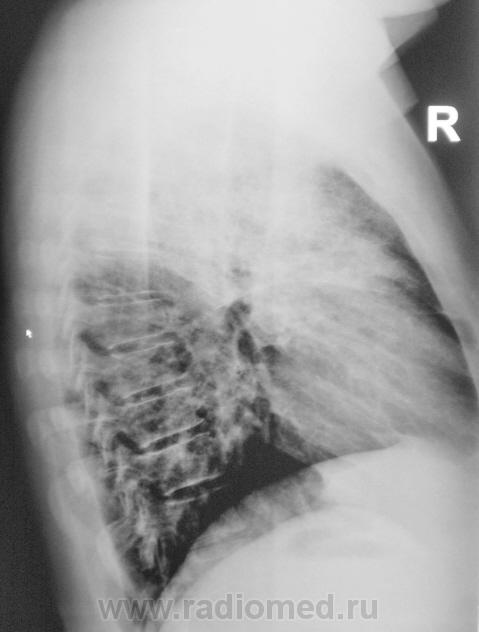

Пациент направлен на рентгенографию ОГК с подозрением на пневмонию.

Валентин Львович и так все знает, что делать, поэтому советовать ничего не буду, только скажу, что пока я за пневмонию.Инфильтрация больше пневмоническую напоминает,междолевая плевра отреагировала,

По прямой рентгенограмме в больших сомнениях пребывал - сомнения по поводу абсцедирования...

Клиника манифестная, на крупозную тянет, "мужик" здоровенный, вчера температура до 40.

Томограммы.